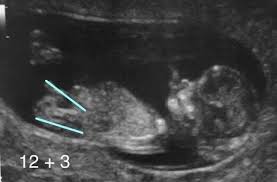

At 13 weeks pregnant infant gender has been defined but the outer genitilia are not completely formed.

The process through which sex is determined is called human sexual differentiation. If you have a prenatal blood test nipt you may be able to find out your baby s sex as early as 11 weeks of pregnancy. At 13 weeks it would be too early sorry. The gender of your baby is revealed at your second scan between 18 and 21 weeks but there s another test people use to determine if it s a boy or girl credit.

Ultrasounds may reveal sex organs by 14 weeks but they aren t considered fully accurate until 18 weeks. Getty contributor the nub theory. If it is moving upward then it is more likely a boy. The flow of urine can sometimes be spotted in a fetus.

Oh i can tell you why they said 80 though. But you re right i was also under the impression that ucl does tell the sex. Around week 12 you can tell the gender with an 80 accuracy at 13 weeks with 95 and so on. Often be seen by weeks 18 to 20 the presence of male genitalia including testicles scrotum and penis is the irrefutable sign of male gender.